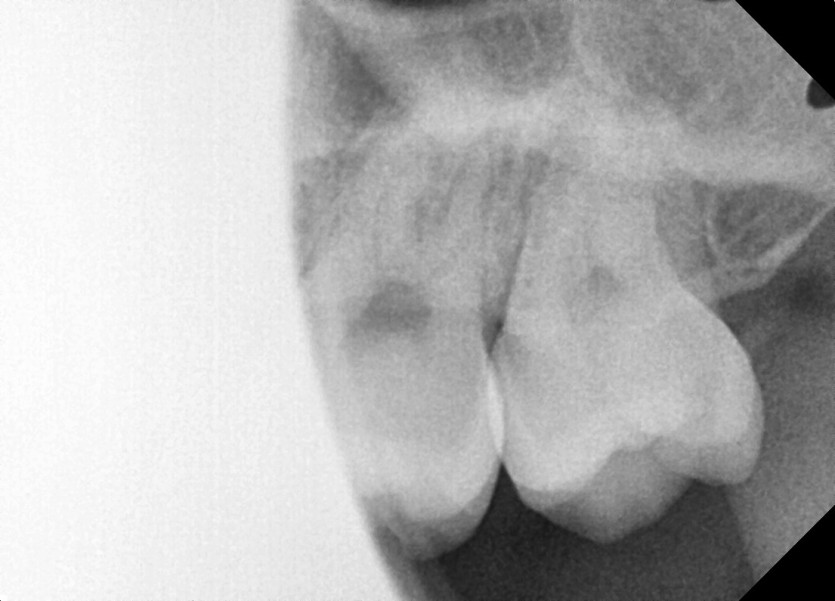

#18,28,38,48 사랑니 발치 (#19과잉치 포함)

구강 외과 전문의가 당일 발치했습니다.